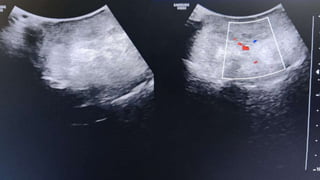

A 38-year-old male presented with a 15 cm pedunculated swelling on his right buttock that had gradually increased in size over 4 years. Ultrasound findings showed a well-defined, lobulated, iso-echoic lesion with minimal vascularity, consistent with a cutaneous fibro-epithelial polyp measuring 15 x 8 cm containing prominent adipose tissue. Fibro-epithelial polyps are typically benign skin tumors of mesenchymal and ectodermal origin that usually occur in skin folds and do not exceed 1-2 mm, but can sometimes reach large dimensions.